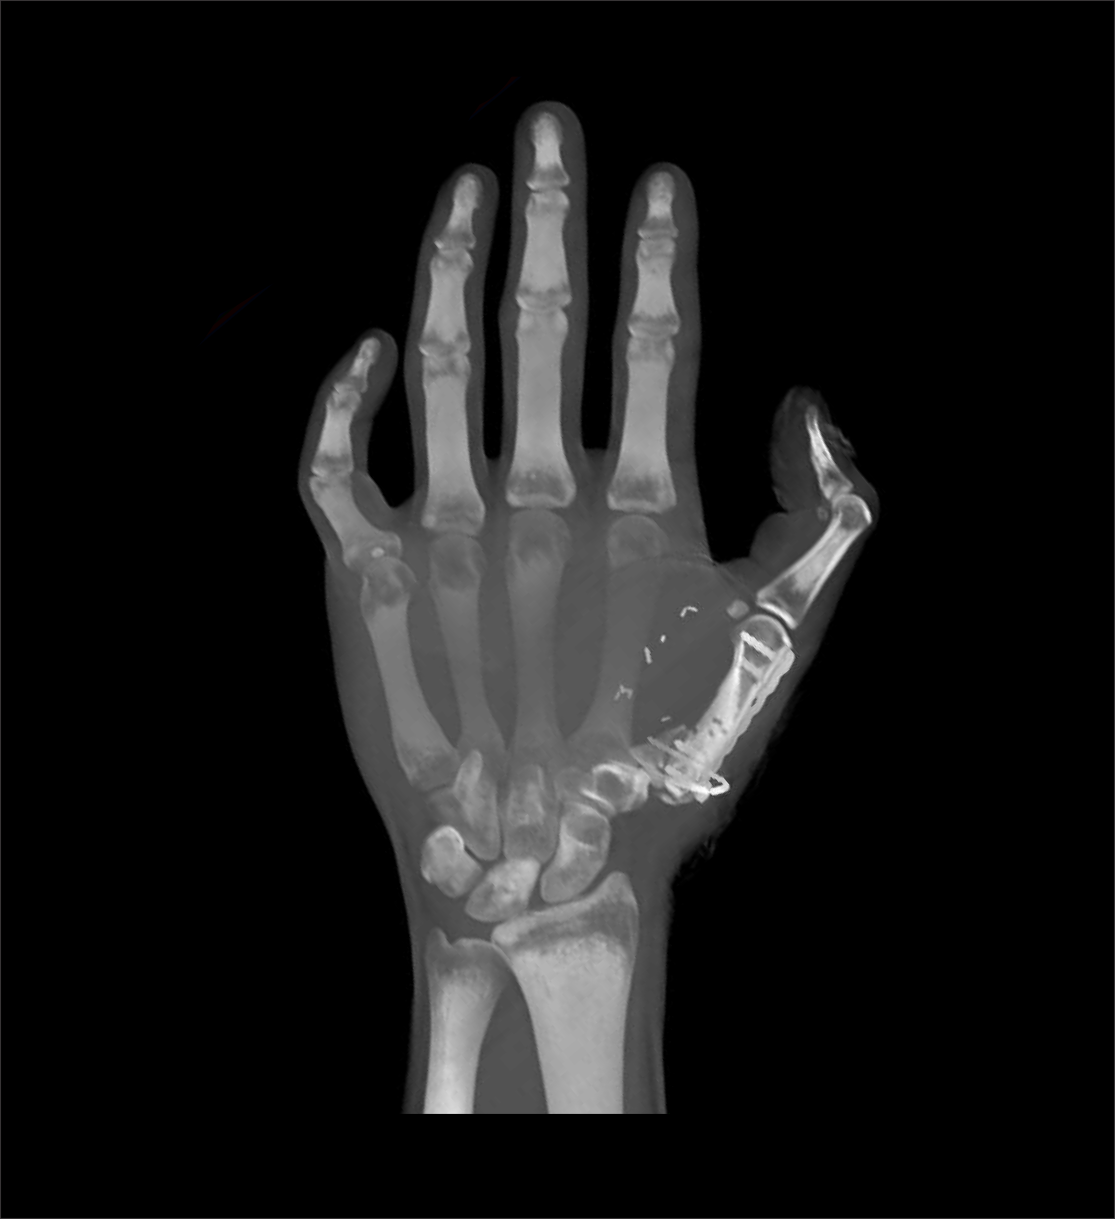

CT hand protocol is used to evaluate conditions such as fractures, implant complications and neoplasm. Its ability to view structures in three dimension (3D) is remarkable for surgical planning.

- 3d images to show pathologies clearly.